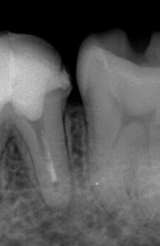

初診時(デンタル) 初診時(CT)

根管充填が不十分で、すき間もあり不良である